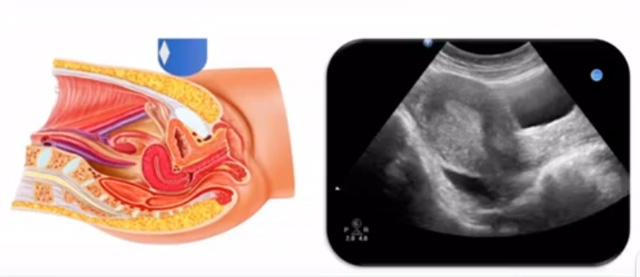

女性生殖系統(tǒng)包括內(nèi)、外生殖器官及其相關(guān)組織以及鄰近器官,其中內(nèi)生殖器是我們超聲檢查的主要對(duì)象。那么內(nèi)生殖器包括陰道、子宮還有輸卵管及卵巢。輸卵管及卵巢稱為子宮附件。子宮是倒置梨形,但是它是空腔厚壁肌性器官。它的正常值在育齡婦女。超聲探頭放在貼近腹壁盆腔上面位置,來看這個(gè)子宮在超聲上面的表現(xiàn)。從輪廓上來講,和示意圖是一樣的。這就是在超聲上面顯示的一個(gè)子宮的圖片。子宮在不同的時(shí)期與子宮頸的比例。成年婦女指的是育齡婦女為2:1子宮體是比較大的,嬰兒期為1:2說明宮頸比較大,絕經(jīng)期1:1。所以我們在看到子宮圖時(shí)候可以根據(jù)宮體宮頸比例大致可以推測屬于哪個(gè)時(shí)期的婦女。另外還可以根據(jù)比例大小來推斷是一個(gè)正常子宮還是異常子宮。

子宮從外到內(nèi),漿膜層、肌層、粘膜層。宮體部宮頸為梭形結(jié)構(gòu)。宮腔為上寬下窄的三角形,連接為峽部。子宮有什么功能呢?月經(jīng)血產(chǎn)生跟排出通道,精子運(yùn)行通道受精作用。囊胚著床及胎兒發(fā)育、生長的場所。分娩時(shí)產(chǎn)生宮縮使胎兒、胎盤娩出。未孕的子宮是很小的,已孕子宮就非常大,平均胎兒都有6斤重。所以這個(gè)后壁就體現(xiàn)出來。輸卵管由子宮角部向外延伸,為一對(duì)細(xì)長而彎曲的管道,呈管狀中空結(jié)構(gòu),大概長度是8-14厘米,粗1-4毫米,它的下方為卵巢和闊韌帶。間質(zhì)部是厚一點(diǎn)的,峽部是比較窄的地方,壺腹部,漏斗部。正常情況下,輸卵管在普通超聲DR難以顯示。